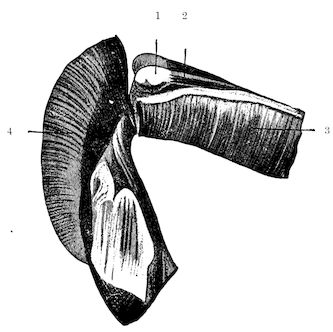

Fig. 9.—C, horn; P, modified skin forming the keratogenous membrane; O, horn core, exhibiting a double sinus.

(2.) The horn-secreting membrane is formed by the skin, which undergoes special development around the base of the horn and comes to resemble that of the coronary band, from which the hoof or claw is secreted. The band is about one-fifth of an inch in breadth. The papillæ of the dermis are specially developed at this point, and the epithelium which they secrete eventually forms the horn.

The internal surface of the growing horn is adherent to the horn core through the medium of another tissue formed by a specially differentiated periosteum which is continuous with the periosteum covering the frontal bone. It is not a true periosteum, but a vascular tissue formed of papillary layers analogous to those of the podophyllous tissue of the ox’s claw or horse’s hoof.

This keratogenous membrane receives a rich vascular supply from the arterial circle formed at the base of the horn core by a division of the external carotid, the blood conveyed by which is freely distributed to the enlarged papillæ. The great vascularity of these parts 23explains why lesions of the horns are often followed by such profuse bleeding.

(3.) The horn secreted by the papillæ of the horn band (which is analogous to that of the coronary band of the horse) forms a cone varying in its curve in various breeds. Its base is hollow, and contains little depressions holding the papillæ from which the horn is secreted. From its base up to the end of the horn core the walls progressively increase in thickness. From this point it is solid; in a fully-grown horn the bone does not extend more than one-half or two-thirds of the entire length.

Anatomy of the horns. The horns form organs of defence, and project on either side of the frontal bone at the poll. Each consists firstly of a bony basis generally known as the horn core; secondly, of a horn-secreting membrane; thirdly, of a horny sheath, the horn properly so called.

22(1.) The horn core projecting from the frontal bone does not develop until after birth. About the third month a little prominence appears under the skin, which, as it develops, assumes a conical shape, and may be seen to be covered with a horny substance. In proportion as the horn core grows, there develops within it a cavity which may either be of a simple character or divided by a longitudinal partition. This communicates with the frontal sinus, a fact which explains the collection of pus in the sinuses as a result of injuries to the horns. The sinus of the horn core does not exist in young animals, and is not completely developed before the third or fourth year of life.